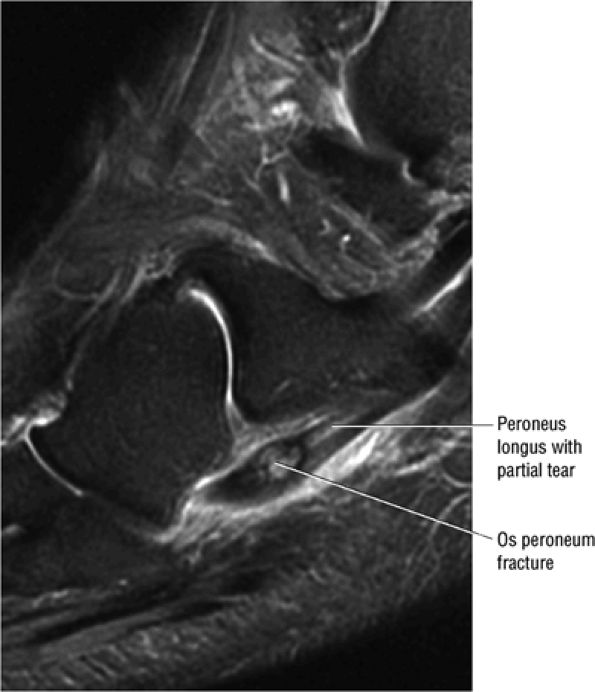

In symptomatic patients there is usually marrow edema and degenerative hyperemia of the subchondral bone.

-